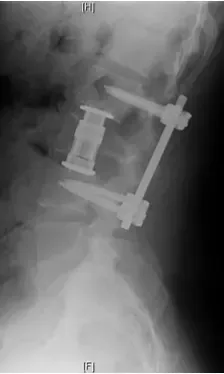

Patient was operated and the spinal canal cleaned up of all bony fragments. The spine was fixed from the side and the back to take care of instability.